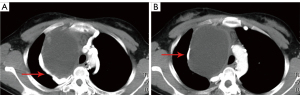

A 21-year-old female presented at our hospital complaining of a chronic cough and coughing up sputum for 10 months. She also complained of chest tightness, shortness of breath, and pain in the right of her back when breathing hard. There was no history of similar symptoms in her family. Right tuberculous pleurisy was diagnosed after a computed tomography (CT). After treatment, the patient was discharged from the hospital and regularly took anti-tuberculosis drugs. Nine months later, the mediastinal mass was larger, and the chest CT showed a quasi-circular water density shadow in the middle and upper mediastinum and indicated effusion in the thoracic and pericardial cavity (see Figure 1). Physical examination revealed no ptosis and the muscle strength was normal.

Tumor resection was performed in August 2018. Pleural adhesion was observed during the operation. The tumor was located in the right middle and superior mediastinum. Cystic fluid pushed outward, oppressing the deep part of the azygos vein arch and superior vena cava. The tumor reached below the right internal jugular vein, the inferior pole was located below the azygos vein arch to the hilum of the lung, and the inside the edge of the tumor reached the right internal mammary vein. The tumor surrounded the superior vena cava, phrenic nerve and azygos venous arch, and its lower part adhered severely to the hilum of the lung, the deep part of the pericardium, and the anterior mediastinum. As bleeding occurred several times during the surgery, and it was difficult to separate the tumor from normal tissues, we resected the tumor by dividing it into three parts. The first part of tumor was the triangular area formed by the superior vena cava, the azygos vein arch, and the right innominate vein. The second part was from the left side of the superior vena cava to the left edge of the tumor. The third part was from the deep part of the superior vena cava to the lower pole of the tumor. During the operation, the integrity of the tumor was destroyed as much as possible, and the surrounding nerves and blood vessels were protected (see Video S1). The postoperative pathology results confirmed a mediastinal mature cystic teratoma (see Figure 2). 1 year later, the chest CT showed that the residual tissue had been absorbed, and the blood vessels were largely restored and had healed well (see Figure 3).